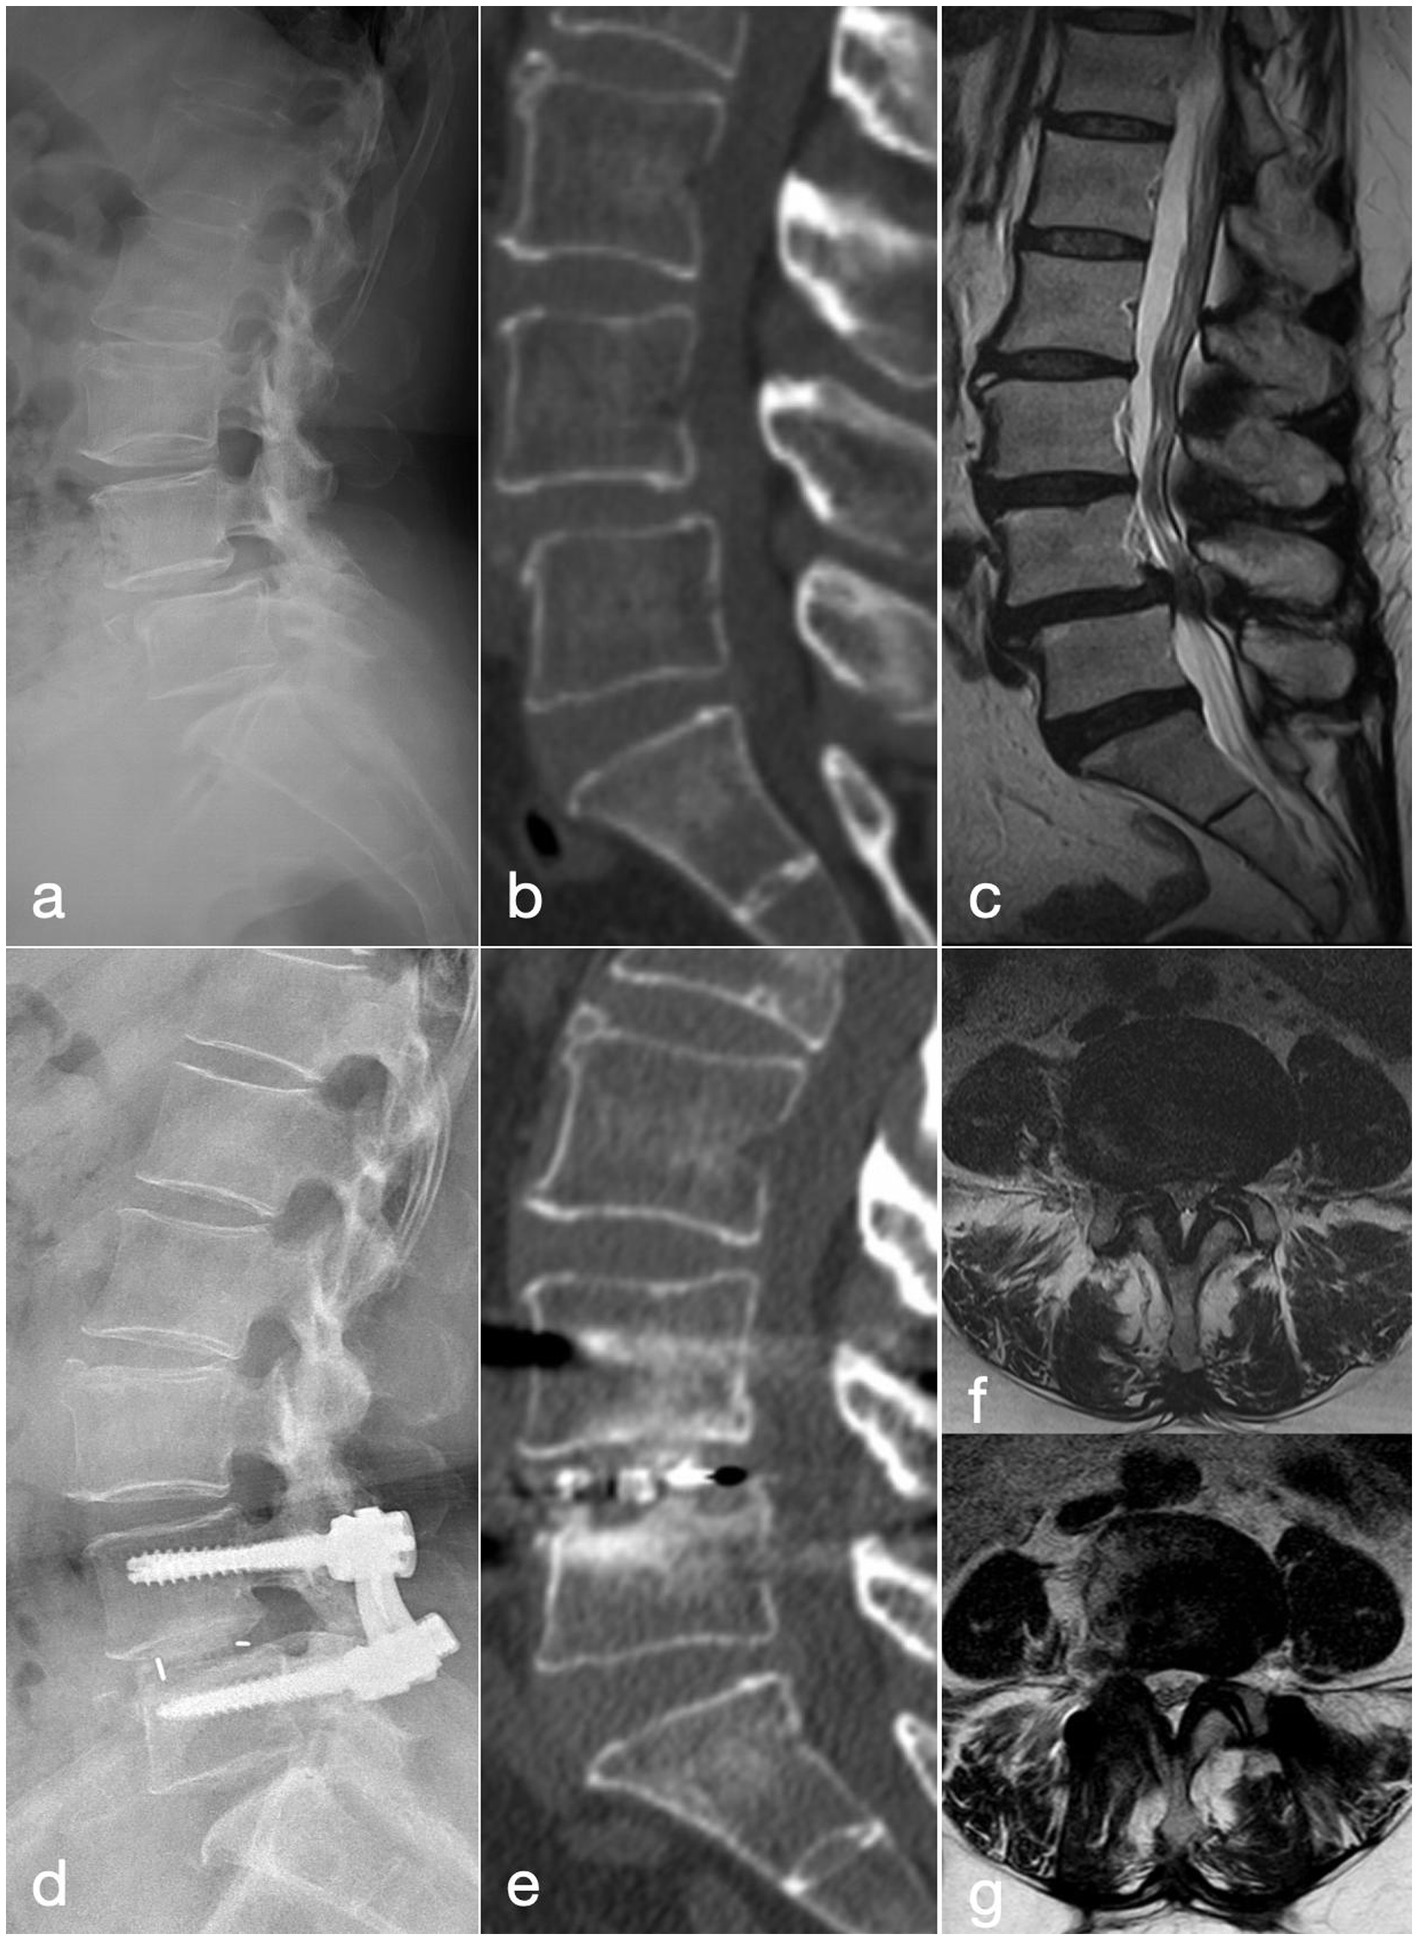

Figure 1

A 56-year-old woman who had been suffering from neurogenic claudication for 1 year, with symptoms worsening over the last 3 months, was treated with the OLIF-AF procedure. (a–c) Pre-operative lateral radiograph, CT and MRI show grade-I anterior spondylolisthesis of L4. (d) Post-operative lateral radiograph demonstrates well-positioned instrumentation and interbody cage with good reduction of the slip. (e) CT at 2 years confirms solid interbody fusion. (f) Pre-operative MRI reveals severe L4/5 central canal stenosis. (g) MRI at 2 years shows increased canal volume and positive nerve-root sedimentation sign.